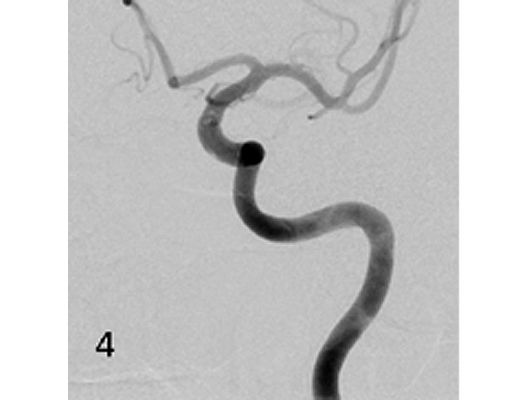

Mit den modernen Verfahren zur Wiedereröffnung von verschlossenen Blutgefäßen können wir Patienten mit Schlaganfall in vielen Fällen helfen. Das folgende Beispiel zeigt die angiographischen Bilder eines Patienten, der mit vollständiger Lähmung der rechten Körperhälfte und einer schweren Sprachstörung eingeliefert wurde. Ursächlich zeigte sich ein Verschluss der linken Halsschlagader, vermutlich auf dem Boden einer arteriosklerotischen Einengung (Bild 1). Das Gefäß wurde daraufhin mit einem Stent wiedereröffnet (Bild 2). Zusätzlich zeigte sich ein Verschluss der Endstrecke des Gefäßes durch Blutgerinnsel (Bild 3). Diese konnten vollständig entfernt werden (Bild 4). Der Patient erholte sich nach der Behandlung innerhalb weniger Tage vollständig.